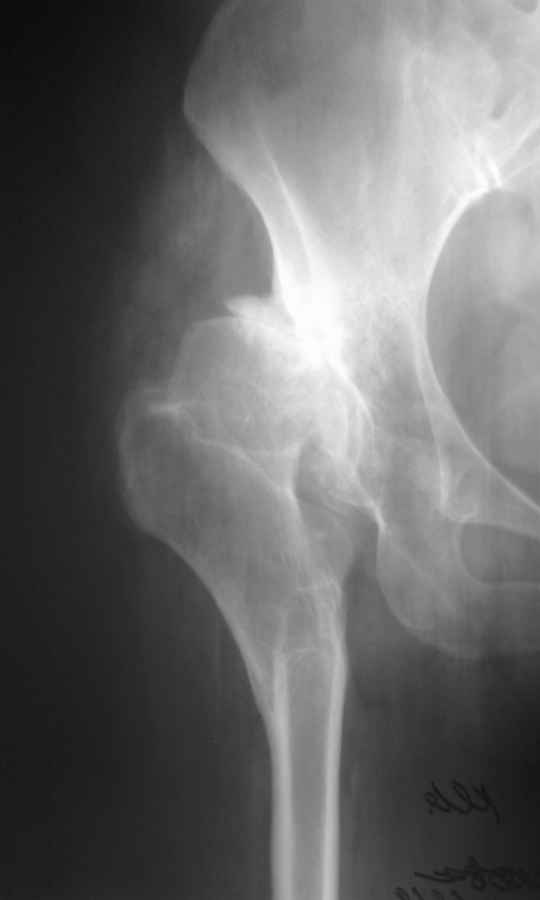

Уважаемый Андрей, ситуация не простая, нет обзорной Р-графии таза, поэтому сложно провести правильное планирование операции. Тем не менее, при планировании операции вертлужный компонент я бы установил в анатомическое положение. В отношении ножки - может быть два решения. Мое предпочтение - (операция типа Paavilaanen'a) поперечная остеотомия бедра на уровне чуть выше деформации, установка ножки Вагнера, скорее всего 190 мм, хотя возможно удастся обойтись и конической ножкой, это зависит от необходимой компенсации длины ноги. Продольная остеотомия б/вертела с последующей фиксацией к диафизу бедра с натяжением мышц. Есть и другой вариант - укорачивающая остеотомия в зоне деформации бедра с установкой ножки со стороны шейки. Мы делали и то и другое, первый вариант проще. В этой операции есть масса нюансов и нужно иметь опыт операций при дисплазии ТБС.

В прищепке случай 1999 года - эндопротезирование после операции Шанца-Илизарова. Возраст пациентки 45. Коррекция была в 17 лет. А Рыков Хабаровск.